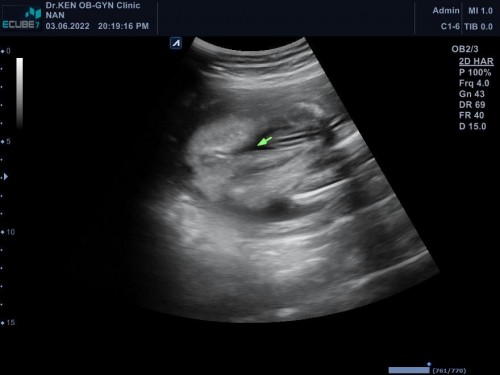

ผู้หญิงรึป่าวคะ ของเราชายจะมีไข่กับจู๋ๆโผล่ตรงหว่างขา

หมอเคยบอกว่าอวัยวะเพศเครื่องหมาย=ก็คือผู้หญิงค่า

น่าจะผู้หญิงคะ

ผู้หญิง100%จ้า